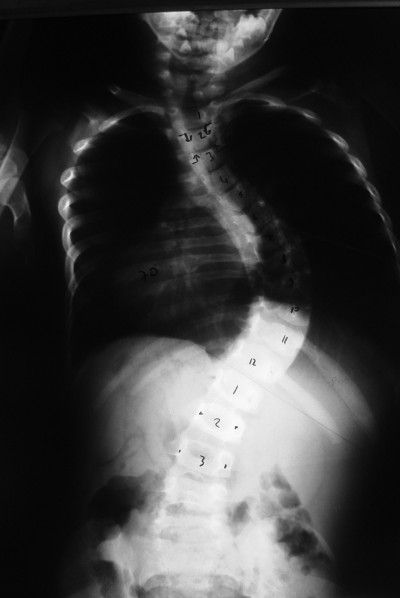

Gövdeye yandan bakıldığı zaman omurgada normal olan eğrilikler görülür. Sırt bölgesinde dış bükey bir eğrilik, kifoz, bel bölgesinde iç bükey bir eğrilik, lordoz vardır. Skolyoz denildiği zaman omurganın yana doğru eğilmesini anlamaktayız. Gövdeye önden veya arkadan baktığınız zaman yana doğru eğiliyormuş gibi bir görüntü verir. Kamburluk veya kifoz ise sırt bölgesindeki dış bükey eğriliğin artmasıdır.

Skolyozun tipik  bulguları her iki omuz yükseklilerinde farklılık, kürek kemiğinin diğerine göre daha çıkıntılı olması, kalçanın diğerine göre daha yüksek veya belirgin olması, bel bölgesinde asimetri gelişmesi, hasta öne doğru eğildiği zaman sırtının bir tarafı diğerine göre daha yüksek görünmesi olarak sayılabilir.

Korse tedavisine yanıt alınamadığı durumlarda cerrahi tedaviye başvurulur. Cerrahi tedavi büyümesi devam eden ve büyümesi tamamlanmış hastalarda farklılık ihtiva eder. Büyümesi tamamlanmamış çocuklarda büyüme dostu implantlar (uzayan rod, magnetik rod, bantlama yöntemi vs.) kullanılır. Büyümesi tamamlanmış çocuklarda ise en sık yapılan cerrahi işlem sırttan vida ve çubuklar kullanılarak enstrümentasyon ve kemik greftiyle yapılan füzyondur. Modern enstrüman sistemleri ile eğriliği %80 oranında düzeltmek mümkündür.